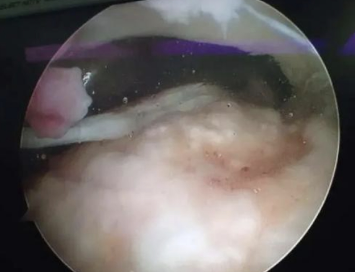

1.關(guān)節(jié)鏡下確診

手術(shù)刀做切口,關(guān)節(jié)鏡進(jìn)到關(guān)節(jié)腔內(nèi)系統(tǒng)性地檢查肩關(guān)節(jié)內(nèi)結(jié)構(gòu)。抓鉗探查撕裂的肩袖,大的肩袖撕裂在關(guān)節(jié)鏡下很容易辨別。鏡下可以發(fā)現(xiàn)肩袖從其肱骨大結(jié)節(jié)的止點(diǎn)上撕脫開,局部形成缺損。關(guān)節(jié)鏡下看到的肩袖撕裂與正常肩袖相比“破了個(gè)洞”。